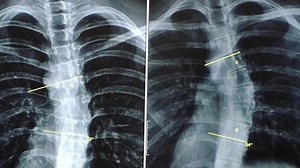

Side Bending Test - Scoliosis Diagnosis

Test - Scoliosis Diagnosis

Shown Medical - Adams Forward

Welding - Adams Scoliosis Test

for Kyphosis